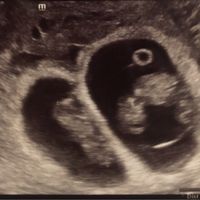

Io dico femmina... Voi invece?

Qualcuna che se ne intende? Io di angoli non ho capito nulla provate a indovinare , forse il 23 agosto riuscirò a vedere il sesso e vi dirò se avete indovinato!!! !

Secondo questa teoria cosa potrebbe essere? Boy or Girl? 💙🎀 Giochiamo un po' 🙂